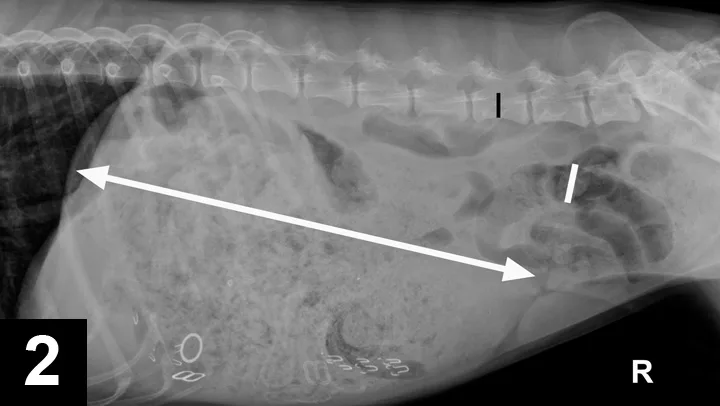

Radiographic Findings: The right lateral view (Figure 2) showed severe gastric distension (white double headed arrow) with granular ingesta, intermediate opacity oval structures seen in the ventral stomach on the lateral view (suggesting rubber bands or hair elastics), and various metallic structures (compatible with bra straps and hooks). The small and large intestines are displaced caudally by the gastric distension. The gas-distended small intestine (white bar) measured up to 24 mm and the height of the L5 vertebral body (black bar) was 11 mm; this gives a small intestinal to L5 ratio of 2.2, which is much greater than the upper limit of 1.6 for normal small intestine to L5 height ratio.1

Comments: It is tempting to see the most obvious radiographic abnormality (ie, the large amount of foreign material) but miss the more subtle abnormality, such as the small intestinal distension in this case. Measuring the distended small intestine and dividing it by the height of the L5 vertebral body (not including the canal and spinous process) can be used as a measure of normal or an abnormally distended (>1.6) small intestinal diameter.